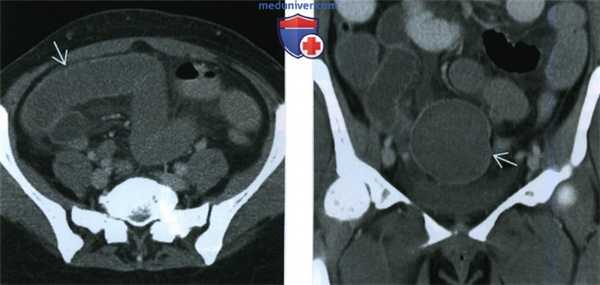

(Слева) При КТ с контрастным усилением в аксиальной плоскости у той же пациентки в обоих легких видны многочисленные солидные узелки с четкими границами. Узелки имеют однородную структуру, по рентгеновской плотности соответствуют мягким тканям и слабо накапливают контрастное вещество.

(Справа) При КТ с контрастным усилением в аксиальной плоскости у той же пациентки видны множественные мягкотканные объемные образования в малом тазу. При биопсии узелков, расположенных в малом тазу и в легких, оказалось, что они состоят из гладкомышечных клеток без признаков атипии и соответствуют по строению миоме матки.